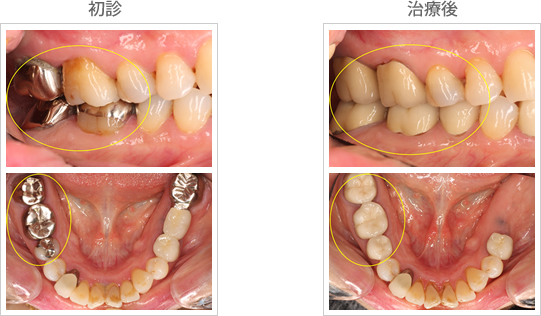

| 60代の女性 奥歯の虫歯の治療とともに、 できれば白くしたいとの希望。 |

歯ぎしり等の 習癖がありませんでしたので、 噛み合わせの面もセラミックスにしています。 |